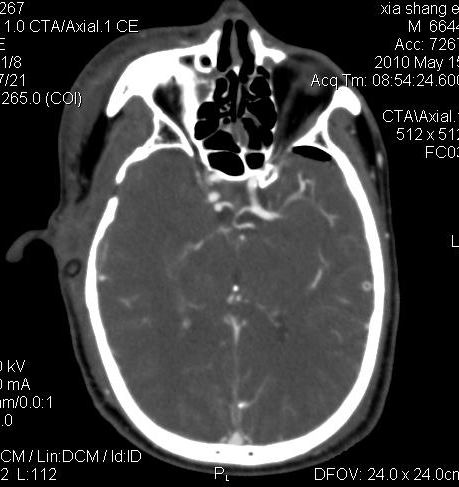

男.60岁,渐进性意识不清,ct检查双侧额颞顶部硬膜下血肿,开颅术后行脑血管cta,大脑中动脉起始部见一瘤状血管扩张。请各位老师留下宝贵意见

太常见了,报动脉瘤就可以

符合动脉瘤表现。

符合动脉瘤表现。

动脉瘤。

颅内动脉瘤。

后重建做得不是很好看,要将维蒂斯环充分显示,最好在增加一个mip。这样不好定位。

小动脉瘤

典型

符合动脉瘤的表现

动脉瘤

符合动脉瘤表现。

小动脉瘤

典型